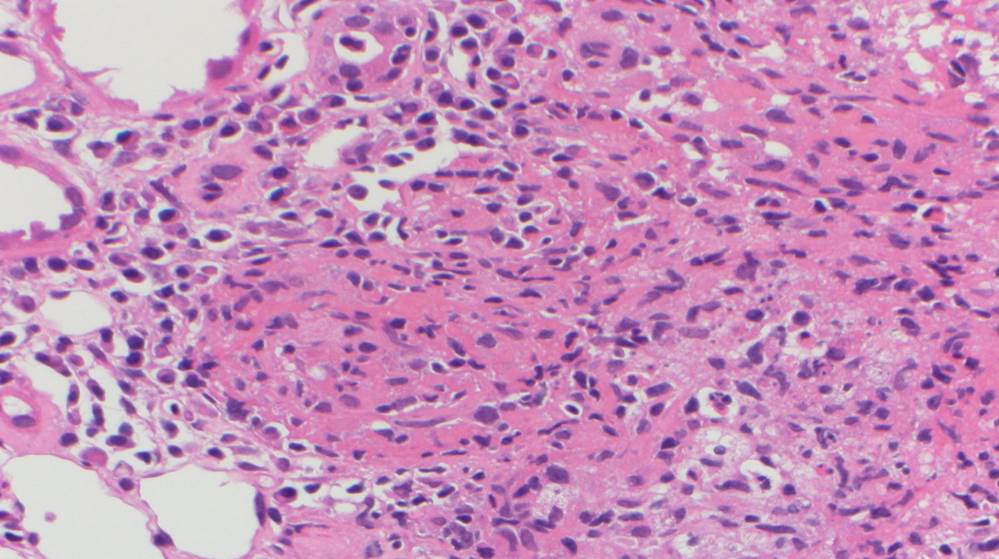

A renal allograft biopsy is essential to differentiate adenoviral nephritis from that of acute rejection or other pathology. Typical light microscopic findings in adenovirus nephropathy include tubular cell necrosis (with tubular basement membrane rupture) associated with severe interstitial inflammation (sometimes with granuloma formation), focal interstitial hemorrhage and viral cytopathic changes including peripheral condensed chromatin, basophilic nuclear inclusions and nuclear enlargement. In some cases such as ours, viral inclusions are not identified, presumably because of the focal nature of viral infection in the kidney. Immunoperoxidase staining can be used to confirm the presence of adenovirus within the nuclei, and to a lesser degree, within the cytoplasm of tubular epithelial cells; although weak, our case showed positive staining. These viral particles are visible under electron microscopy, measuring approximately 75 nm, however they were absent in our patient. Diagnosis in such cases can be clinched by urine examination showing white cell casts and decoy cells, and PCR on the urine testing positive for viral DNA.